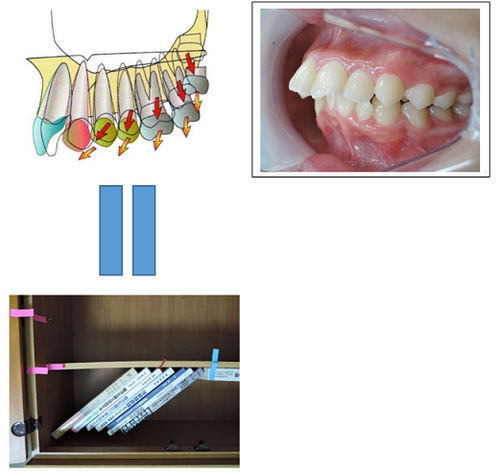

臼歯部が何らかの理由で近心部の歯を押し出していくメカニズムは上下ほぼ同じです。

下の図は歯の押し出しが前歯まで影響を与えている症例です。

大臼歯部が近心に傾いて咬み合わせの高さが低くなるとその歪みが前歯に伝わり、前突状態となります。

MEAW(マルチループ)を利用して歯を動かす隙間の作り方は2種類あります。

②ふたつ目は以下の様な原理です。

①では歯が近心側に綺麗に傾いた場合ですが、歯が内側(舌側)に傾く事もあります。

この場合もMEAW(マルチループ)によって内側(舌側)に傾むいた歯を起こしていきます。

MEAW(マルチループ)を利用して歯を動かす隙間の作り方は2種類あります。

①ひとつ目は以下の様な原理です。

これを身近な7冊の本を使って説明していきましょう。